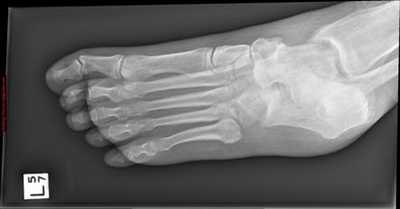

Рентгенография используется для определения угла между линиями, проведёнными между первой плюсневой костью и проксимальной фалангой первого пальца. Если угол больше 15°, подтверждает диагноз hallux valgus. Если угол составляет 45-50° — консервативное лечение не показано. Также должны быть определены степень смещения сесамовидных костей и уровень остеоартрита первого плюсне-фалангового сустава.

Тестирование пациента должно осуществляться два раза: в положении сидя и стоя. В положении стоя деформация стопы наиболее выражена. Во время исследования также необходимо обратить внимание на плоскостопие и степень натяжения ахиллова сухожилия, высоту продольного свода и положение большого пальца по отношению к остальным.

Если неоперативное лечение не помогло, необходимо рассмотреть вопрос о хирургическом лечении (уровень доказательности: 4). Перед выполнением операции необходимо определить степень тяжести hallux valgus. Для этого следует выполнить рентгенографию стоп в положении стоя.